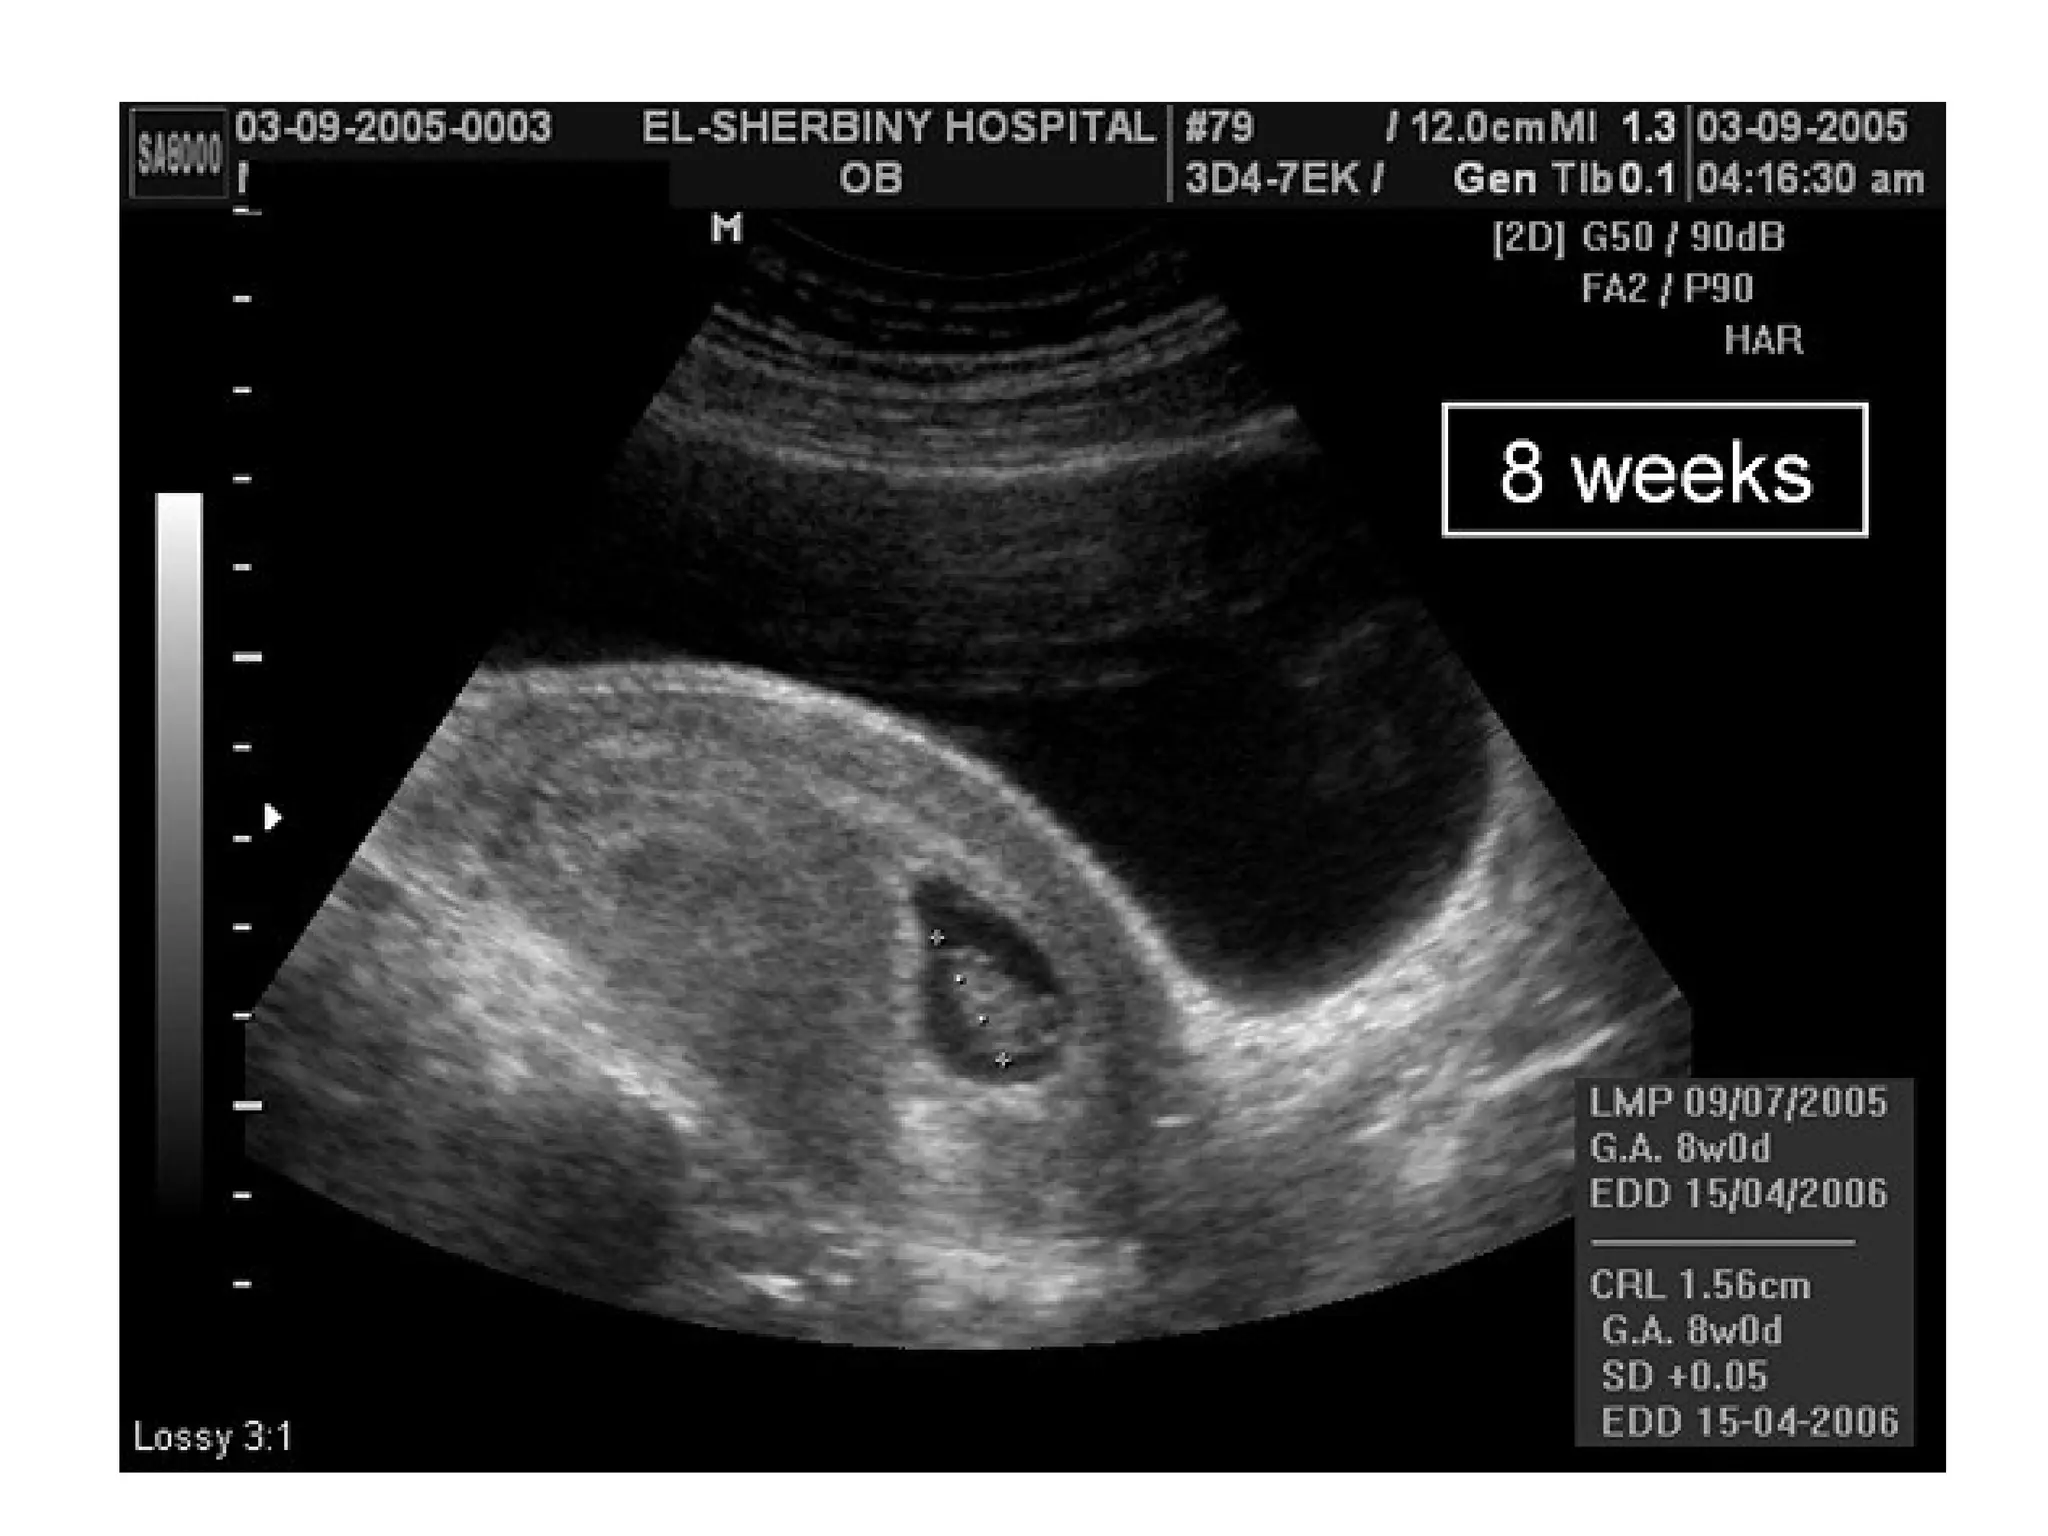

Molar pregnancy information. ultrasound included.

pregnancy molar ultrasound